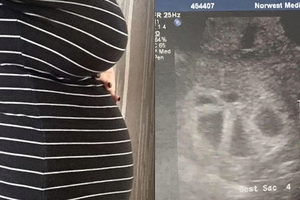

她產檢時才發現懷的不止一個,「寶寶數量」多到數不清,連醫生都嚇傻了!沒想到「超音波」竟照到了...